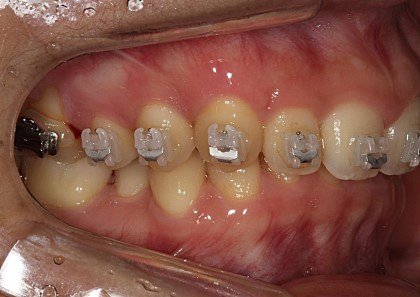

초기진료 때 찍은 잇몸상태 사진을 첨부합니다.

ㄷㅇ치과 원장은 이런 제잇몸 상태를 항상 괜찮다 해왔습니다..사진보고 놀라지 마세요..

ㄷㅇ치과에 초기부터 잇몸이 항상 아프다. 출혈이 자주있고 양치할때도 아파서 잘 못닦는다 하였지만, 대표원장의 대답은 늘 괜찮다는 말이었습니다.

하지만 강남구청역 모 치과 원장님은 이런 잇몸 상태로는 교정하기 힘들다며 치주전문 병원에 연계해 주어 급히 잇몸이식수술을 받아야했습니다

이날도 왼쪽 잇몸이 너무아프고 출혈이 심하게났어서 얘기했지만 괜찮다고 하며 어떤치료도 없었으며, “뿌리가 3개 있는 쪽이라 괜찮다”하길래 믿었습니다.

이곳에서 “현재 잇몸 상태로는 교정을 진행할 수 없으며, 치료와 잇몸 수술 후에 교정해야 하므로 연계 병원에서 수술부터 해야 할 일이다”라는 설명을 들었습니다.

이곳 원장은 저의 상태를 내버려둔 채 교정을 진행해온 사실에 경악하더군요.